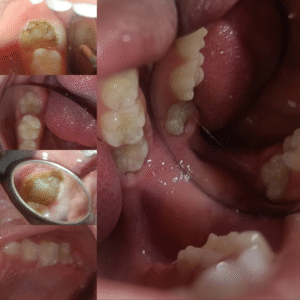

Răng trẻ em

- Sealant dán bít hỗ rãnh phòng ngừa sâu răng

- Công nghệ thấm nhập nhựa, trám không cần mài răng – ưu việt cho răng thiếu khoáng (thiểu sản men)

- Dịch vụ làm răng trẻ em nhẹ nhàng, không tiếng “khóc”

- Niềng răng sớm cho trẻ giúp định hình xương, hàm và răng tối ưu để định hình cho sự phát triển toàn diện nhất

- Cắt thắng môi, thắng lưỡi ngắn (bám thấp) gây ảnh hưởng đến bộ răng, chức năng ăn/nói của trẻ ở độ tuổi thích hợp

- Bộc lộ sớm răng ngầm, răng khó mọc để hàm răng được ổn định và phát triển toàn diện